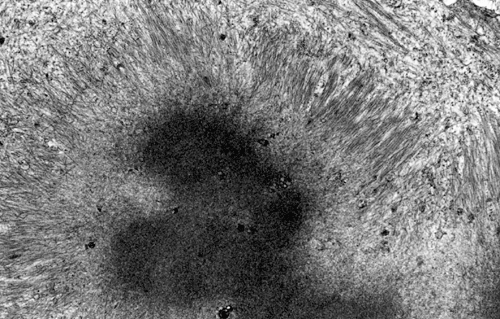

On hematoxylin-eosin stained sections, there is an increased variation of fiber diameter with many atrophic fibers intermingled with fibers of normal caliber. There is no evidence of fiber grouping or perifascicular atrophy. No inflammatory cells are present. There is also mild interstitial fibrosis (Panel A). On higher magnification, many fibers have a round concentric structure (Panel B). Irregular, centrally located depositions are also identified on modified Gomori's trichrome. The concentric nature, however, is not as obvious as in the hematoxin-eosin stained sections (Panel C). Type I and II fibers are not clearly separated in the ATPase preparation at pH 9.4. This is a common situation in chronically ill muscle (Panel D). The type I fibers are unusually dark. There is an increase in the proportion of type I fibers. The atrophic fibers are usually type II fibers. The concentric lesions are found predominantly in type I fibers (Panel E). There is an increase in PAS staining which is consistent with increased glycogen storage (Panel F). No increase in lipid content is demonstrated by oil red O (Panel G). On NADH-TR reaction, the concentric structures appear to have a clear central core that is devoid of enzymatic activity, a rim with intense enzymatic activity and a surround zone with relatively normal reactivity. These features are classic for target fibers (Panel H and I). No deficiency of laminin-2 (merosin) (Panel J) or dystrophin (Panel K) is demonstrated by immunohistochemistry. The central lesions are also immunoreactive for both laminin-2 and dystrophin. Immunohistochemistry for desmin demonstrate a core of strong immunoreactivity and also strong reaction in the sarcoplasmic membrane (Panel L and M). The target structures are also well demonstrated on semithin sections (Panel N). On electron microscopy, z-disc streaming is a common finding and they are often admixed with a substantial amount of dense granular electron dense substance (Panel O and P). There are also numerous cytoplasmic bodies characterized by radiating intermediate filaments (spheroid bodies) (Panel Q and R).

The two major pathologic findings are inclusion bodies and granulofilamentous material. Type I fibers are predominantly affected. Inclusions are eosinophilic on hematoxylin-eosin stain and bluish on modified Gomori’s trichrome stain. These inclusions are often negative for oxidative enzymes. A strong reactivity for desmin can be demonstrated by immunohistochemistry. The abnormal accumulation can occur as cytoplasmic inclusions, subsarcolemmal inclusions, spheroid bodies (10-20 mm oval or spherical inclusions), and patches or “hyaline structures”. In some cases, there is Z-disc streaming but no masses are demonstrated by trichrome stain. Numerous negative areas may be demonstrated by oxidative enzyme reactions. An accentuated intermyofibrillar network is seen by antidesmin antibody staining. Under the electron microscope, spheroid bodies appear as cytoplasmic bodies with a dense, granular core surrounded by fine filaments in a coronary arrangement. Although they are conspicuous on light microscopy, they may not be as distinctive at the ultrastructural level.

Granulofilamentous materials, also known as dappled dense structures” are dense anatomosing and trabeculated granular material that is about 100 nm in diameter is accumulated in between myofibrils or under the sarcolemma. The Z-disc streaming may appear contiguous to the granular deposits. They also appear as “non-hyaline” structure on immunofluroesent microscopy.Cytoplasmic bodies characterized by radiating intermediate filaments (spheroid bodies) are also common.